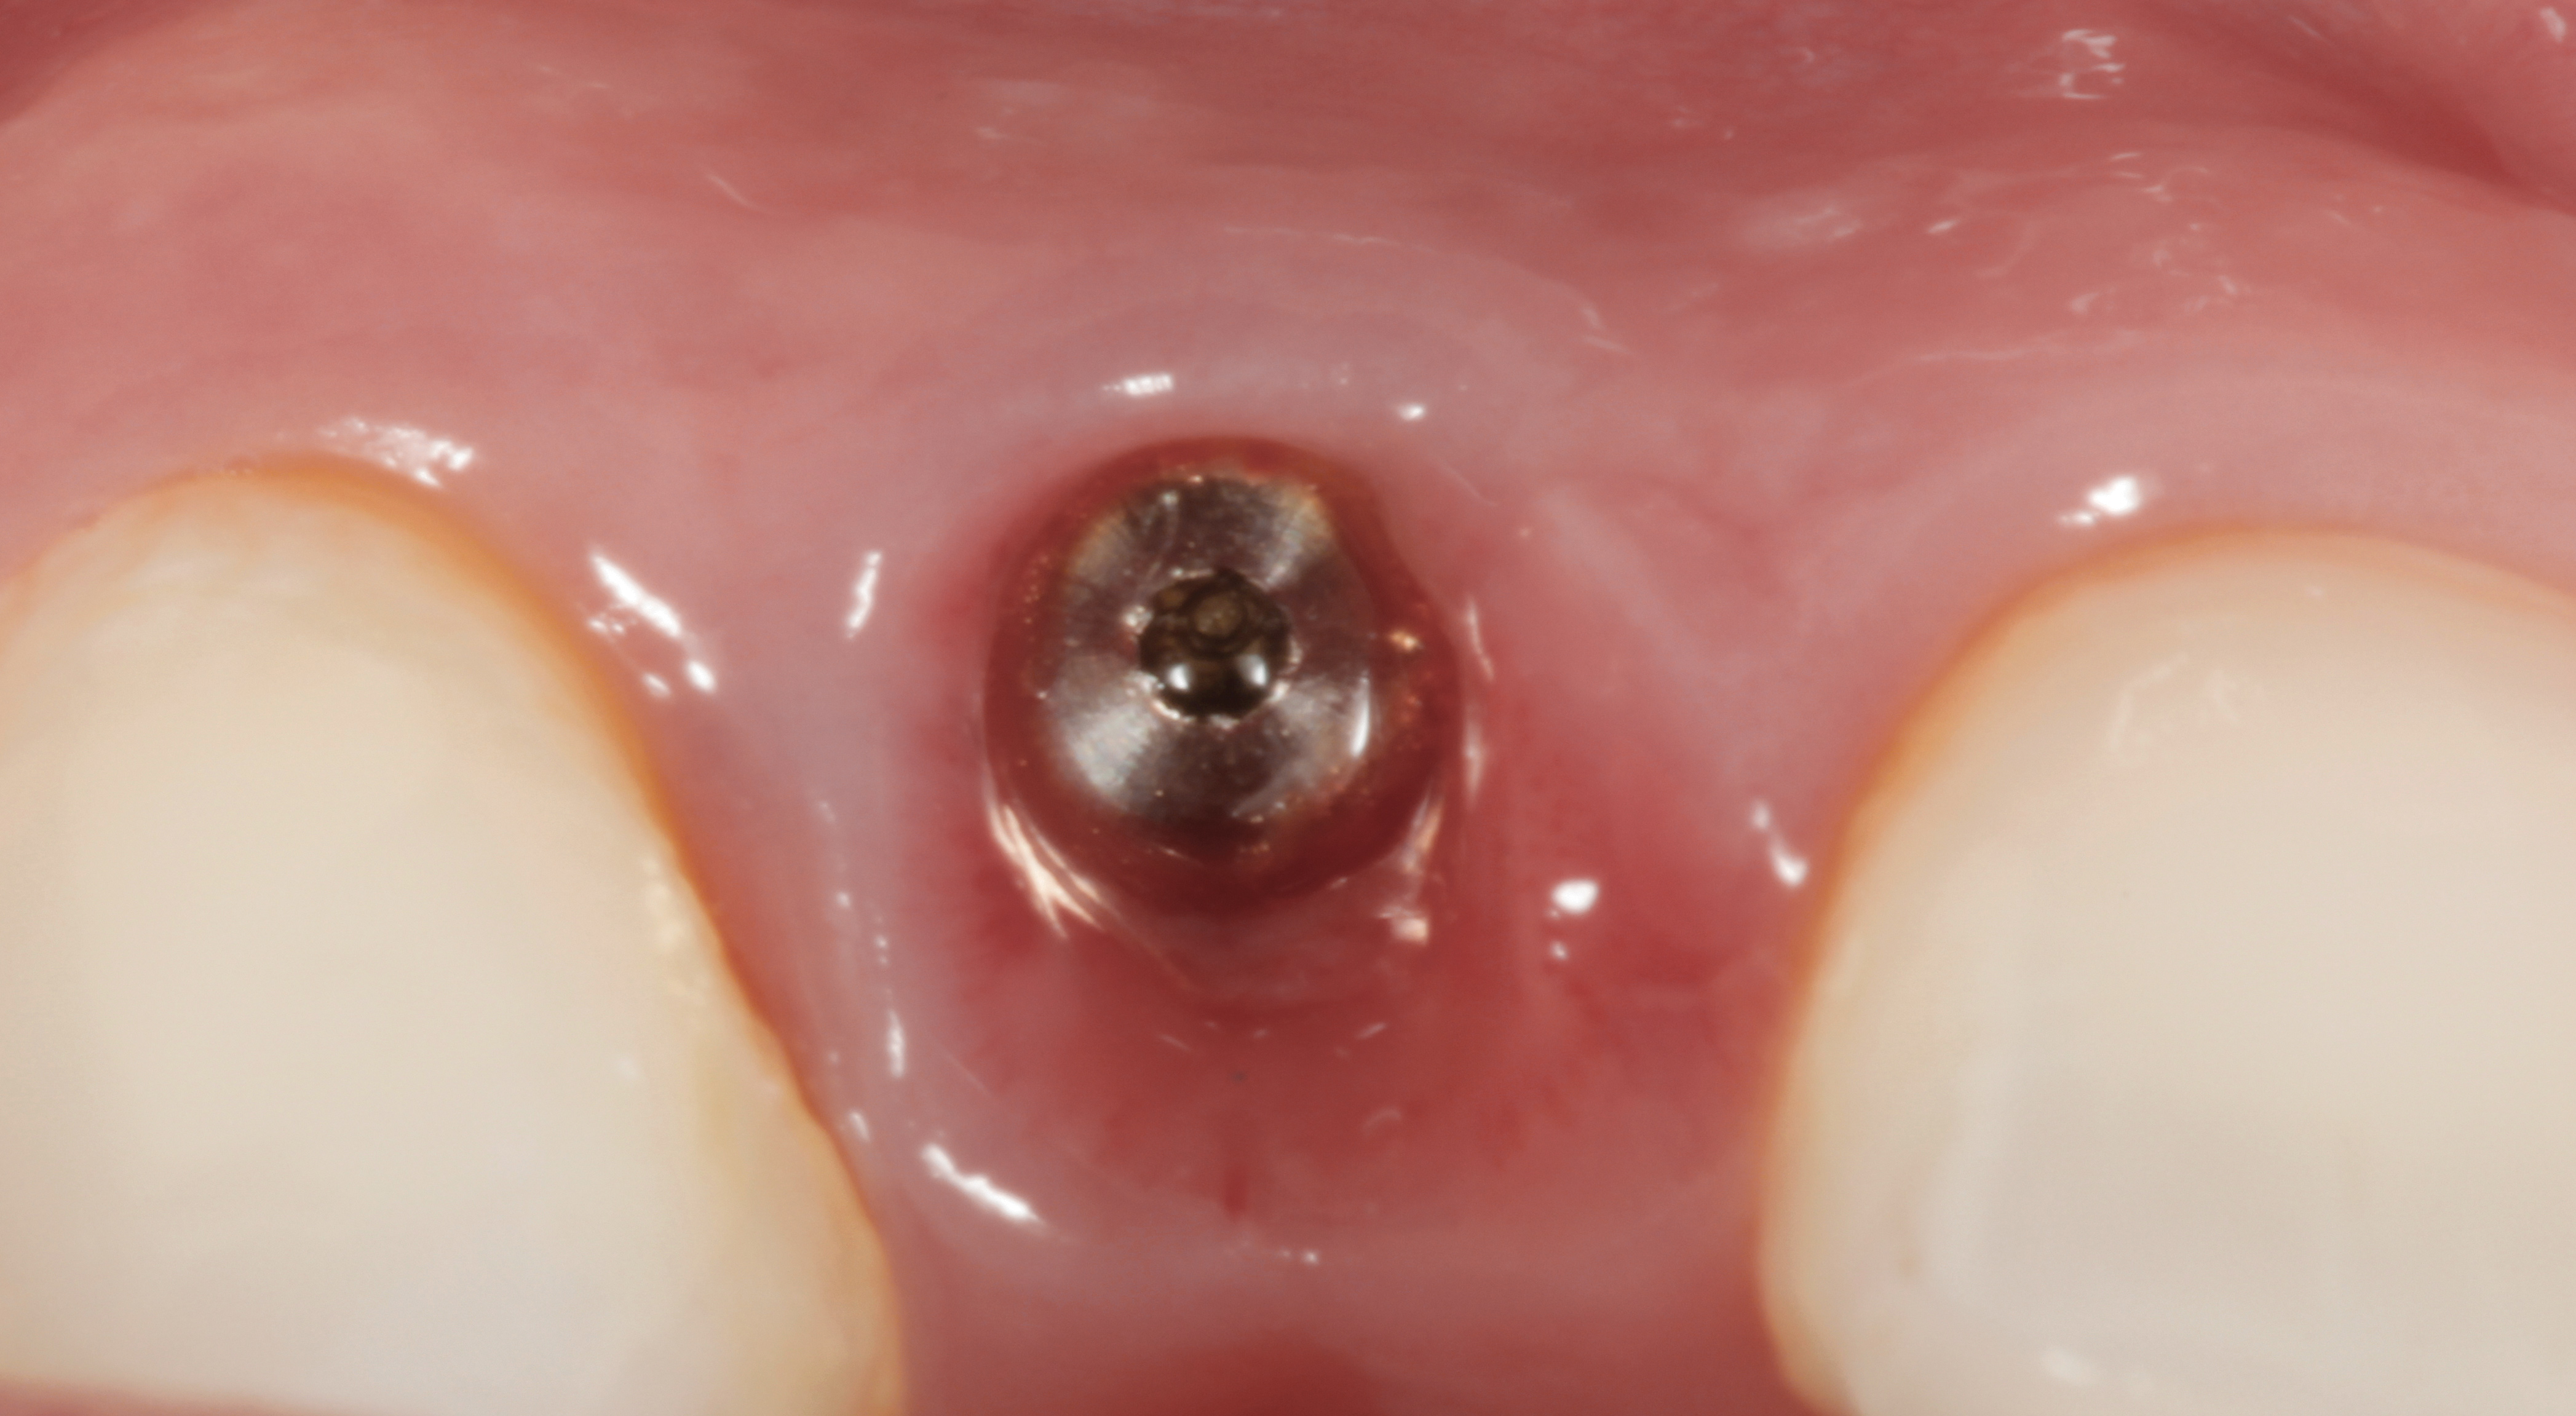

The following case report provides an example of this case scenario: A 24-year-old white male presented with congenitally missing tooth No. 26 restored with a single-tooth cement-retained implant restoration. The implant was placed excessively to the facial aspect of the edentulous site and too shallow, and the periodontal phenotype was thin scalloped (Figure 32). In an effort to mimic the lost midfacial soft tissues, pink ceramics were used as a cosmetic facade. Even though the restoration was not in the esthetic zone, the patient was highly displeased with the esthetic outcome and sought remediation.

The crown and screw-retained custom abutment were removed, and a surgical cover screw was placed into the implant, thereby allowing spontaneous gingival augmentation in situ (Figure 33 and Figure 34). Note that the lingual aspect of the implant site was significantly more coronal than the labial aspect, which was positive because the defect would be limited to a facial–lingual defect. A fixed RBR bridge was cemented on the adjacent teeth and used as a tooth-supported transitional provisional restoration (Figure 35). A few weeks were allotted to let the soft tissue heal and migrate around the cover screw (Figure 36) to see if there would be complete coverage, thereby allowing a soft-tissue augmentation procedure to be performed with primary flap closure as in clinical scenario No. 2. The major obstacle in achieving a positive tissue response was that the implant depth was also deficient because the implant–abutment connection was at the level of the free gingival margin. It was decided that the best treatment option would be to remove the implant. A high-powered reverse-torque device (Fixture Remover Kit, NeoBiotech, www.neobiotechus.com) was used to remove the implant atraumatically (Figure 38 through Figure 41). The implant socket was allowed to heal for several months not unlike an extracted tooth (Figure 42). A new implant was placed in a better position from both a restorative and esthetic perspective (Figure 43), and after a few months of healing, a new crown was made (Figure 44). A satisfactory functional and esthetic result was achieved (Figure 45 and Figure 46) without employing pink porcelain.

Fig 32. A dissatisfied patient presented with significant midfacial recession of implant restoration of tooth No. 26. Pink ceramic material was used unsuccessfully to prosthodontically compensate for the lost midfacial tissue.

Fig 33. Excessive facial angulation of the implant placement shown with an abutment driver in the access screw hole.

Fig 34. A surgical cover screw was placed in an attempt to decoronate the implant and gain soft-tissue coverage in situ.